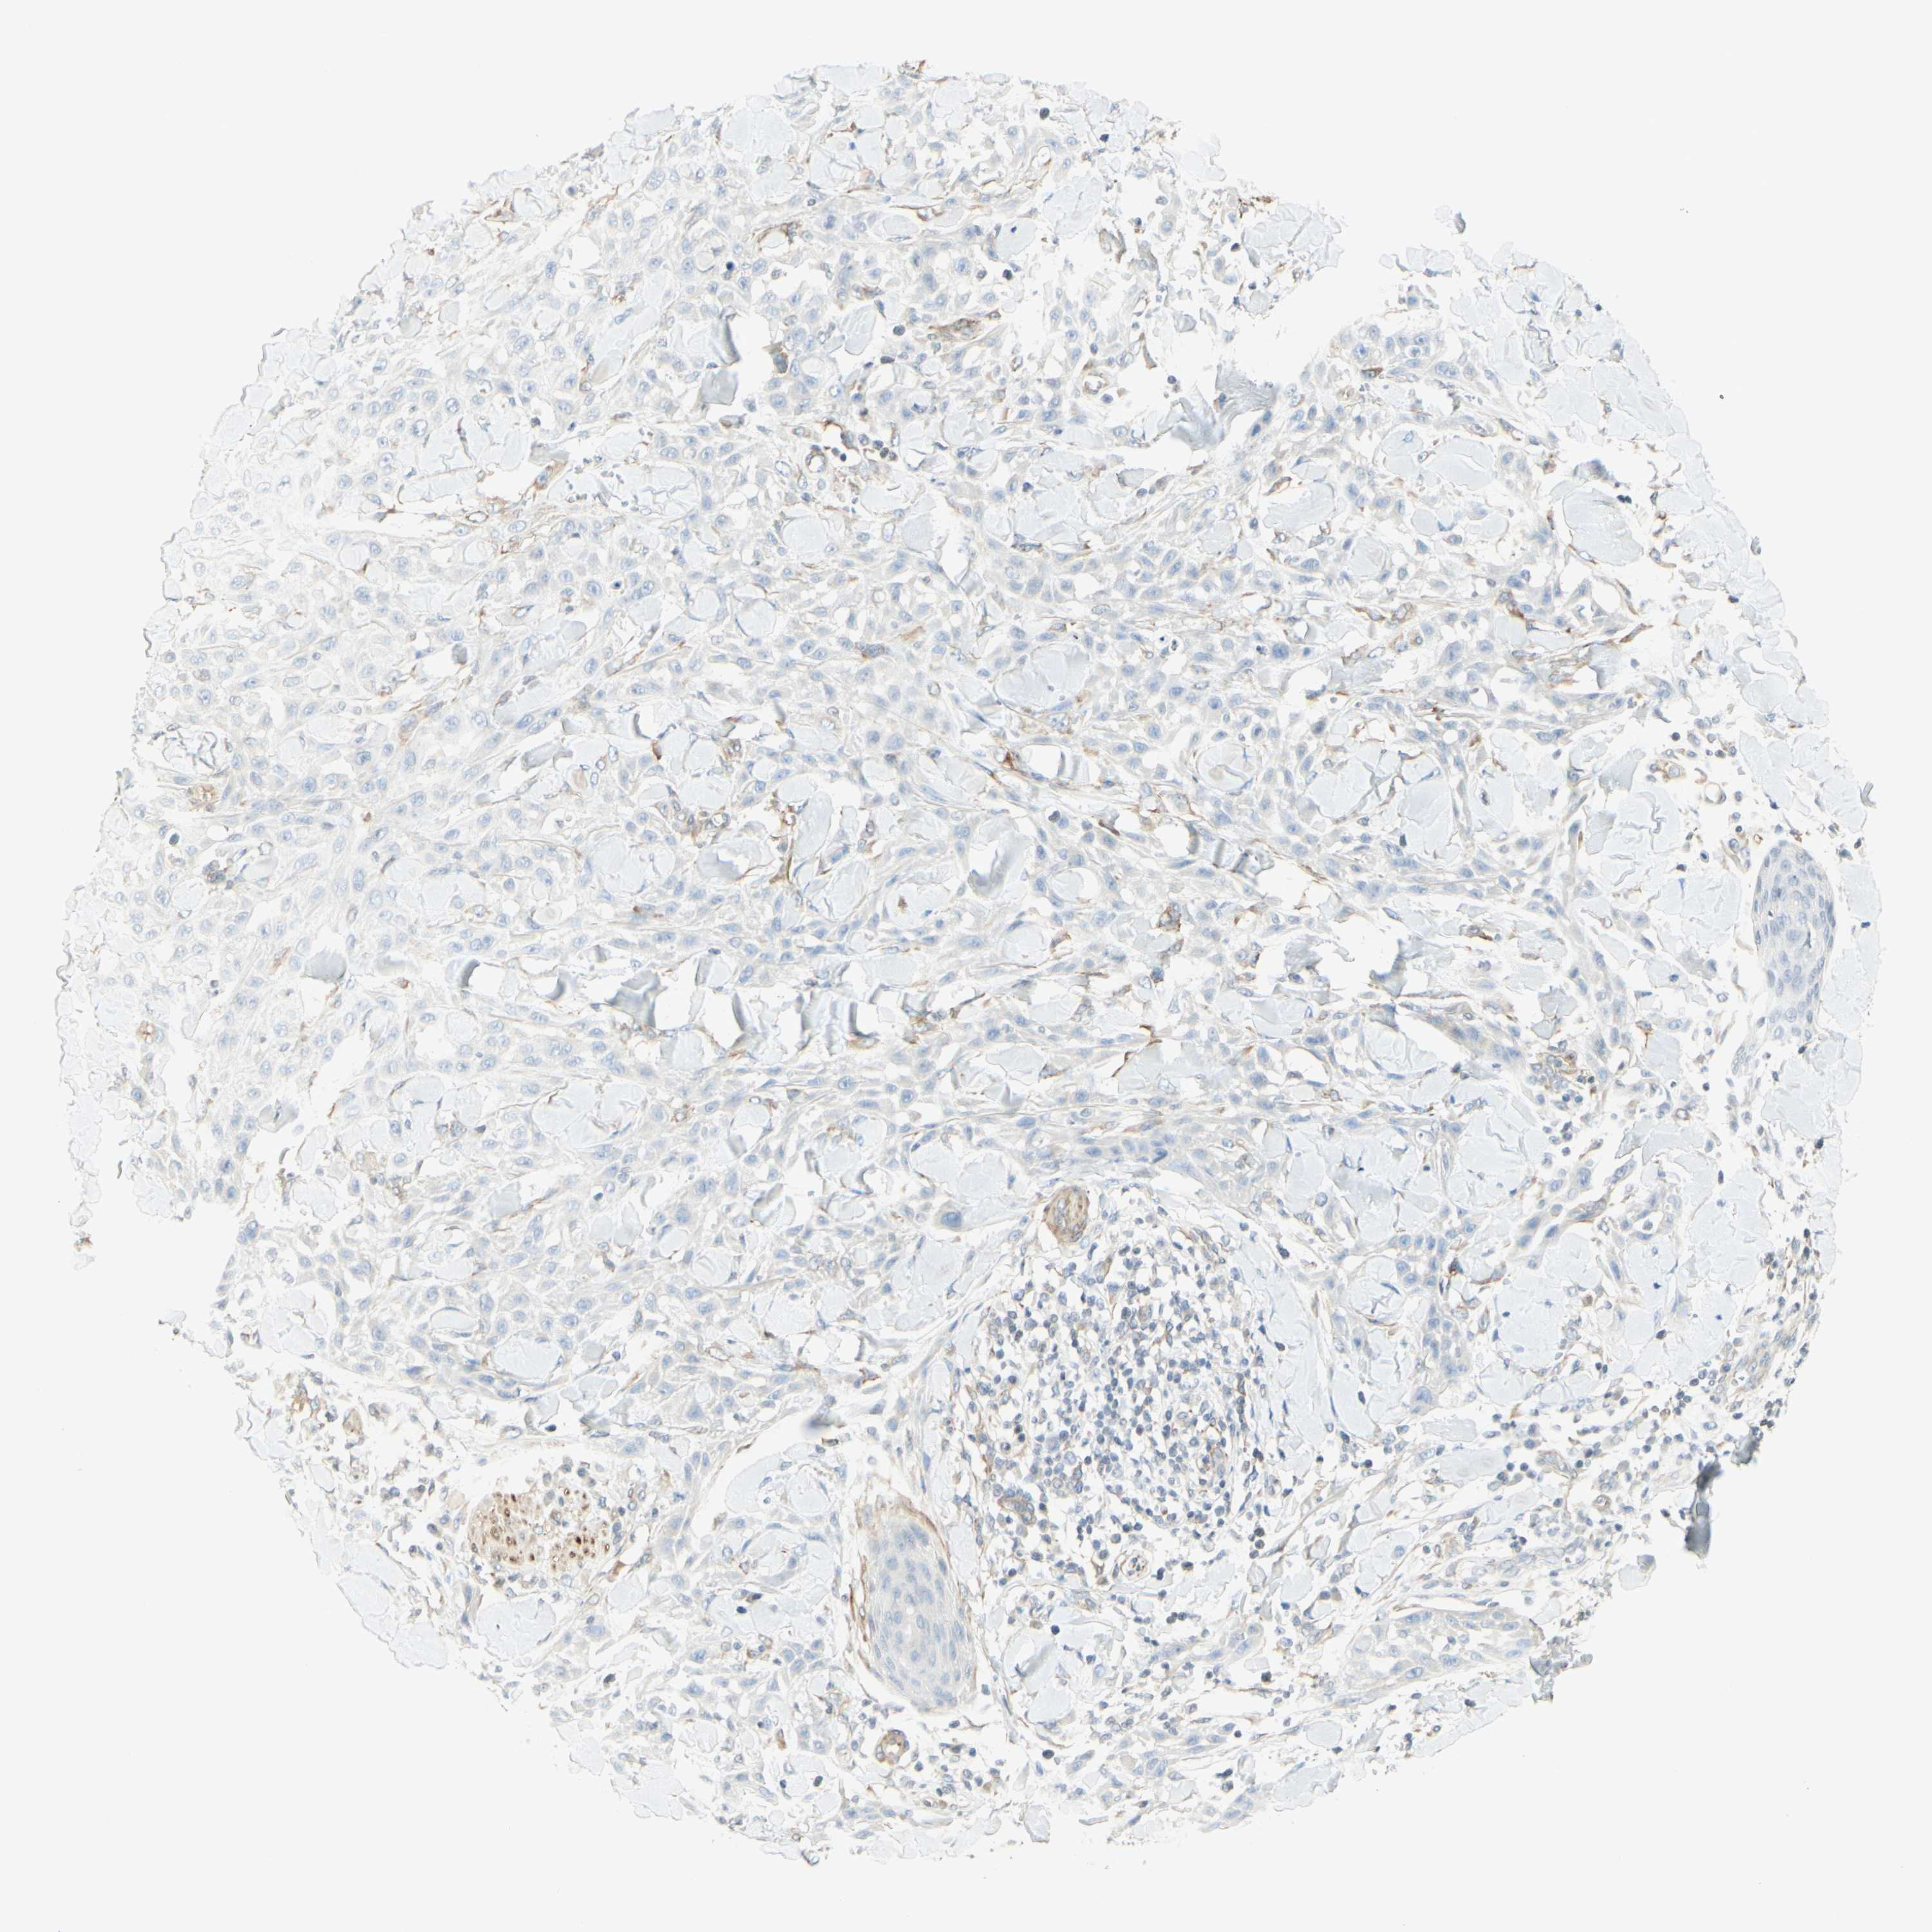

SKIN CANCER - Protein expressioni

A mouse-over function shows sample information and annotation data. Click on an image to view it in a full screen mode. Samples can be filtered based on level of antibody staining by selecting one or several of the following categories: high, medium, low and not detected. The assay and annotation is described here.

Antibody stainingi

Antibody staining in the annotated cell types in the current human tissue is reported as not detected, low, medium, or high, based on conventional immunohistochemistry profiling in selected tissues. This score is based on the combination of the staining intensity and fraction of stained cells.

Each image is clickable and will lead to virtual microscopy that enables deeper exploration of all samples and also displays staining intensity scores, fraction scores and subcellular localization as well as patient and tissue information for each sample.

Antibody HPA022275

Antibody CAB009792

Basal cell carcinoma

Squamous cell carcinoma, NOS

Squamous cell carcinoma, metastatic, NOS